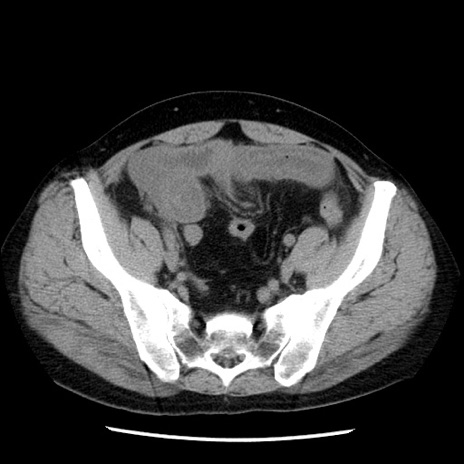

冠状断像

【症例】40歳代男性

【現病歴】2日前から胃痛あり。徐々に周期的な激痛に変化した。本日になっても激痛があるため受診。

【身体所見】意識清明、BT 38-39℃台あり、腹部:膨満、やや硬、右下腹部に圧痛あり。

【データ】WBC 8500、CRP 23.26